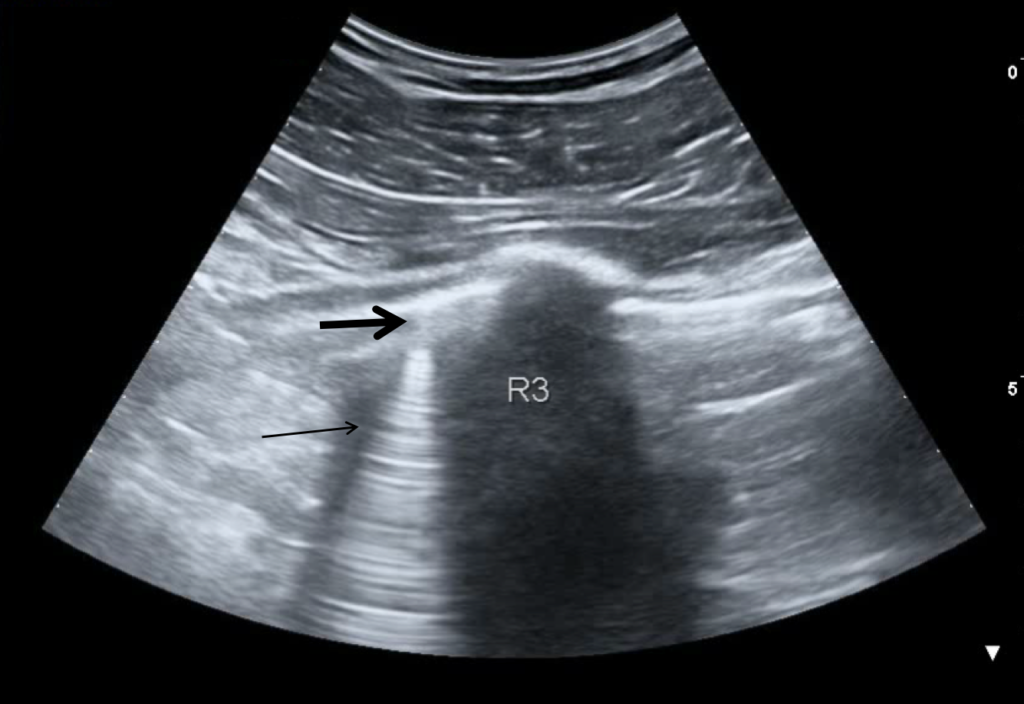

Video 1: Lung consolidation in the basal segment of the lower right lobe after patient deterioration (day 2).

A 30-year-old man presents to the emergency department (ED) due to syncope. For the last 10 days he had had fever, cough and dyspnea. At the ED his peripheral oxygen saturation was 86%, BP 130/80, HR 88bpm, RR 20 /min and his temperature 37.4°C. He was given oxygen via a mask. Chest CT was performed and later lung ultrasound (LUS) was performed in 12 areas longitudinal/oblique views using a convex array probe followed by a linear array probe for details (figure 1).

The patient tested positive for SARS-COV-2. On day 2 after admission the patient’s condition deteriorated, and he was transferred to the ICU. Another chest CT was performed. We show the ultrasound and CT images with corresponding legends (image 1-7 + video 1) and discuss the findings in relation to the diagnostic work-up of COVID-19 pneumonia.

On imaging, initial lesions are usually peripheral because SARS-COV-2 attacks the small distal airways. Several reports have described the findings in chest CT. Most commonly few, small, segmental ground glass opacities are seen peripherally and basal. These may deteriorate to become bilateral and multisegmental and finally consolidation and/or ARDS. Most common LUS signs are: vertical pleurogenic artifacts with varying degree of intensity (from few to confluent). These alternate with clear demarcation to A-lines in the same area, especially in the mid- and upper lung. Pleural thickening, sometimes marked, due to the presence of numerous, small subpleural consolidations. Lobar or translobar consolidations of large size and minimal pleural effusions. The LUS features match with the site and kind on CT.

LUS is an examination, which can be carried out bedside. It may provide early information of presence of diffuse multifocal pneumonia (as in COVID-19) and its deterioration (enlarging consolidations). By doing LUS in cases with COVID-19 pneumonia, transport of patients through the hospital and unnecessary exposure of staff and other patients is avoided. Similar LUS signs as the ones described have been observed in other kinds of viral epidemic pneumonia. If they, individually or in combination, have some specificity for COVID-19 pneumonia it should be established with further appropriate studies.